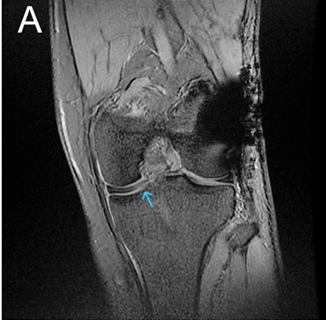

Posterior Approach for Single-stage Fixation of Medial Hoffa with Posterior Cruciate Ligament Avulsion: A Rare Case Report

Meghal Goyal , Kishor Munde

………………………………p.99-103